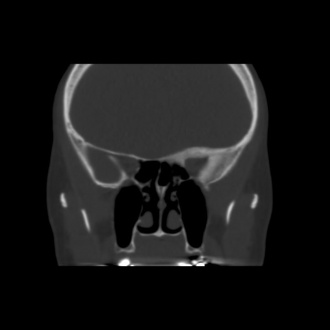

Diagnostic procedures

Fibrous dysplasia was initially studied using plain X-rays, and its characteristic mottled, sclerotic appearance described as resembling “ground-glass.” Today, lesions may be well characterized on computed tomography. The radiographic features vary based on the proportion of normal, mineralized bone to fibrous tissue in any given lesion. Early in the disease course, cystic and sclerotic areas are noted. As dysplasia progresses, a heterogeneous “pagetoid” pattern of radiolucent and radiopaque areas is seen, reflecting regions of fibrous stroma and opaque, osseous changes, respectively. [11][4] Typically, fibrous dysplasia has smooth cortical margins and no soft tissue involvement. [3][11][2] On MRI, lesions are low to isointense on T1 and T2-weighted images, and demonstrate moderate enhancement with gadolinium. [5][4][1]

Radiographic optic nerve bony encasement is exceedingly common in craniofacial fibrous dysplasia, and may approach rates as high as 50-90% of patients. [14][21] The relationship between optic canal stenosis and visual compromise is uncertain, however, as large studies have demonstrated that the majority of patients with completely encased nerves remain asymptomatic without evidence of optic neuropathy. (Figures 1 and 2) [10][14][16]